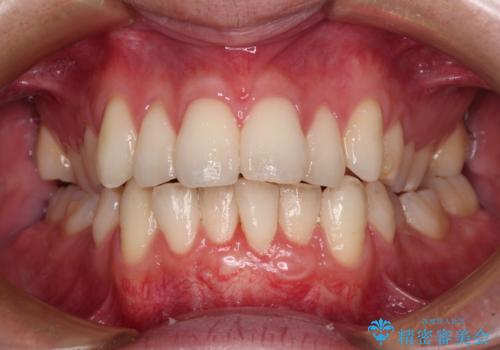

1回目の処置で多少は被覆され歯肉が厚くなりましたが、十分とは言えなかったため、2回目の処置を行いました。

2回目の処置後には十分な厚みと、十分な被覆量を獲得することができました。